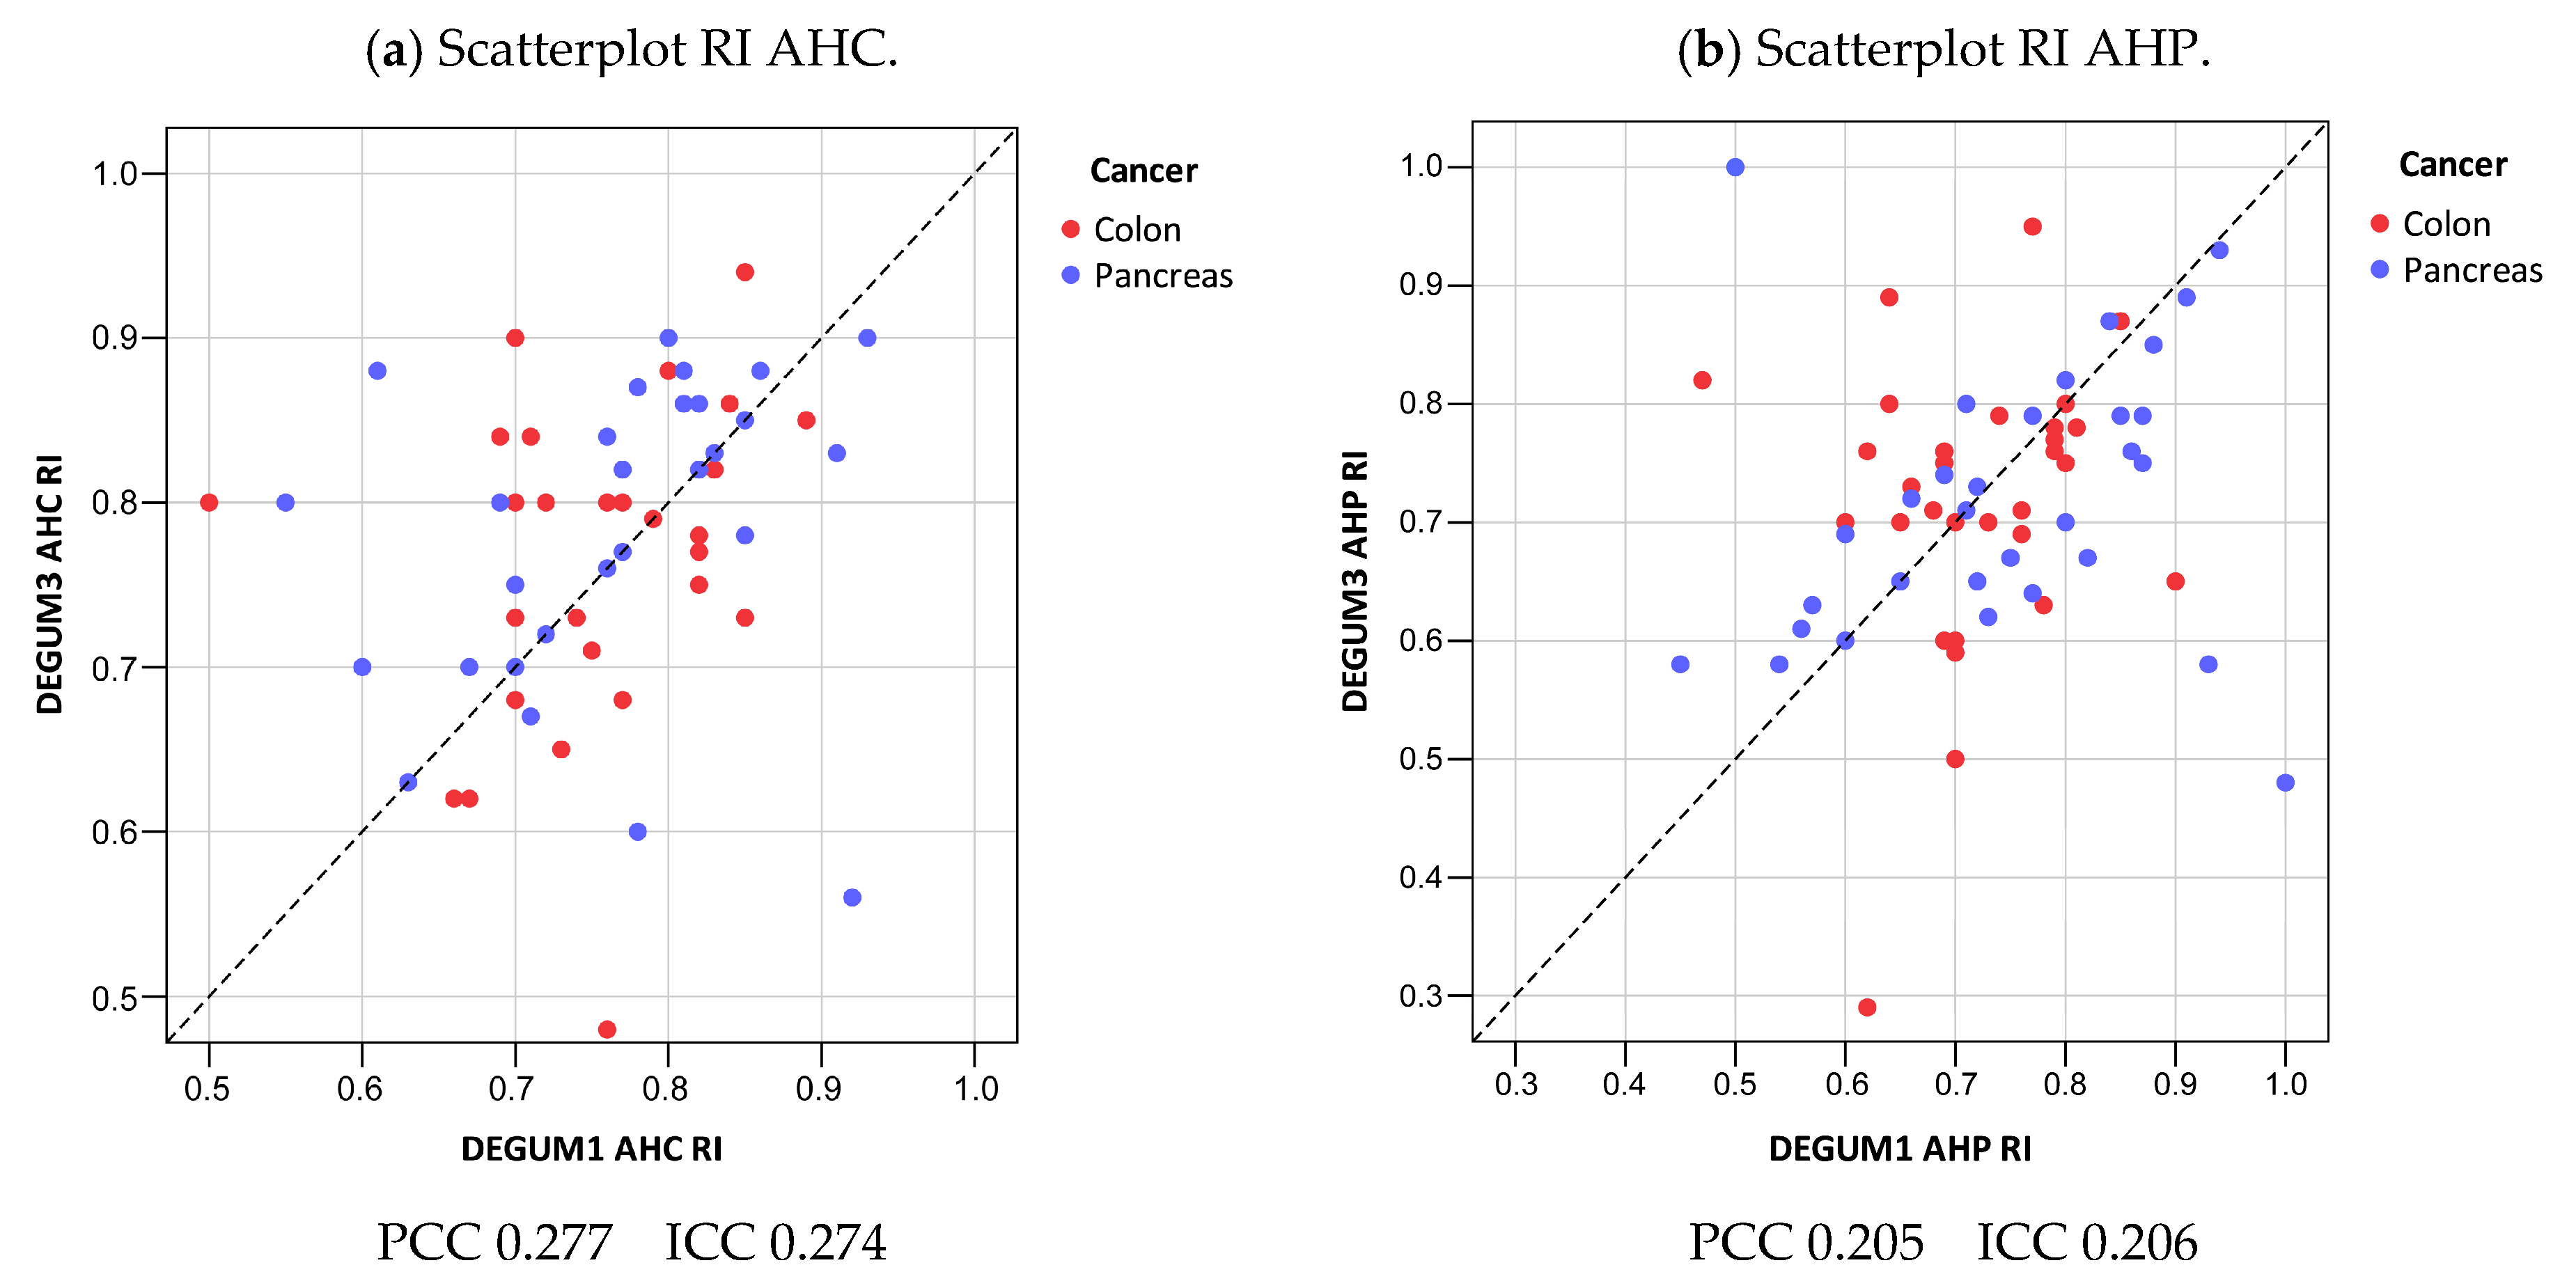

3.4. Resistive Index